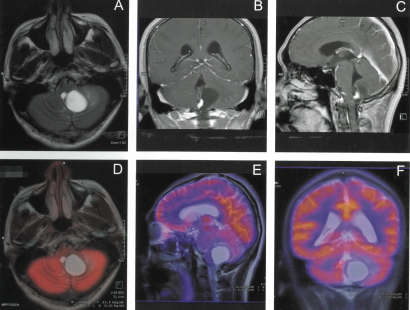

某血管网状细胞瘤PET/MR影像示例

PET/MR

也称派特磁共振,是由PET、磁共振成像(MR)两强联手而成的前沿影像设备,通过两种影像技术的准确匹配与融合,能实现同步采集、定位准、消除运动伪影的效果,同时有着可全身扫描、没有CT那样的辐射伤害等特点,在脑部肿瘤检查方面也有着明显的优势。